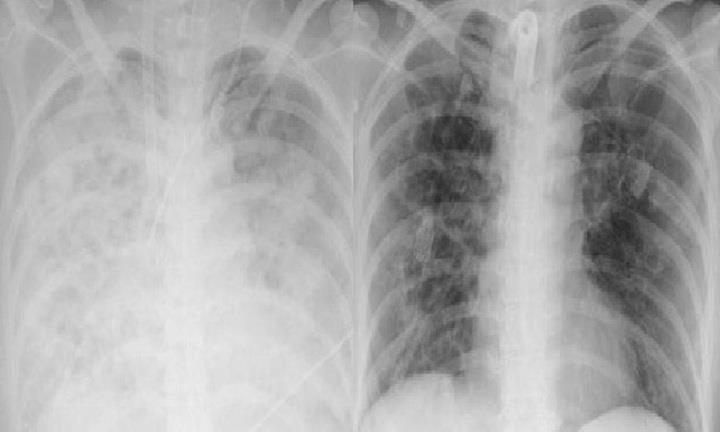

Các bác sĩ Bệnh viện Bạch Mai vừa cứu người phụ nữ bị viêm phổi bội nhiễm, suy đa tạng do lạm dụng corticoid tự điều trị cúm.